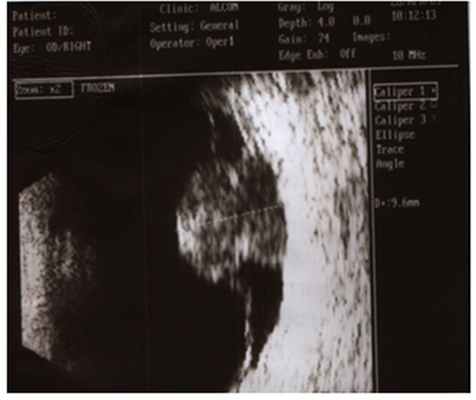

2. Ультразвуковое исследование – ведущий метод диагностики опухолей глаза. Методика проведения контактная и безболезненная. Сканирование позволяет «увидеть» опухоль при непрозрачных средах глаза, установить ее размеры.

Янченко Т.В. изучала частоту и распространенность ретинобластомы на территории Кемеровской области. Автором доклада был проведен анализ обследования и лечения 58 детей (77 глаз) с ретинобластомой за период с 1984 по 2013 годы. Ранняя диагностика опухоли дает шанс пациенту к органосохранному лечению; снижение частоты энуклеации возможно только при своевременной диагностике ретинобластомы (рис. 1).

Профессор Саакян С.В. в своем выступлении дала историческую справку о ретинобластоме, рассказала о системной и локальной химиотерапии, определила место интравитреальной химиотерапии в составе комбинированного лечения ретинобластомы, доложила о результатах и осложнениях после проведения ИВХТ. Докладчик считает, что, несмотря на выявленные побочные эффекты, ИВХТ является ценным методом лечения запущенных форм ретинобластомы с эндофитным характером роста и массивной диссеминацией опухолевых клеток по сетчатке в составе комбинированного лечения ретинобластомы групп D и E (рис. 2).

Горшков И.М. представил результаты комбинированной схемы лечения пациентов с меланомой хориоидеи после эндорезекции опухоли, предложив собственный подход. Эндорезекция в ряде случаев может быть альтернативой энуклеации при лечении «больших» меланом хориоидеи (Рис.3). Несмотря на то, что данный способ лечения предполагает, как правило, повторные хирургические вмешательства, несомненным его преимуществом является реальная возможность сохранения глаза и зрительных функций.